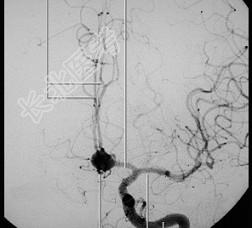

- 单项选择题如图所示脑动脉瘤的定位应该为 ( )

A、右颈内动脉

B、前交通动脉

C、左大脑前动脉

D、右大脑前动脉

E、左颈内动脉